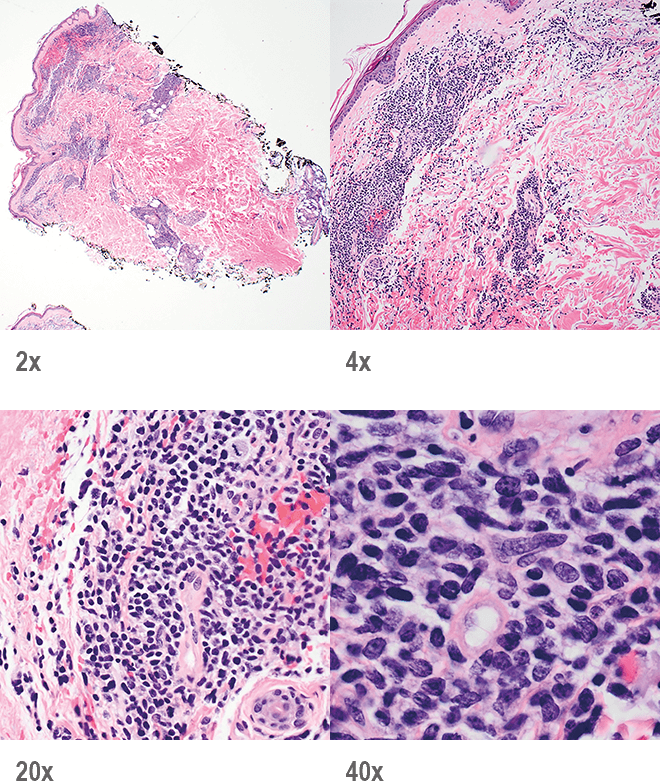

Recognizing BPDCN: Morphology

Punch biopsy of a skin lesion showing BPDCN Punch biopsy of a skin lesion showing BPDCN

Skin

Punch biopsy of a skin lesion showing BPDCN (H&E stain, x40) and (inset) medium-sized malignant cells spare the epidermis (H&E stain, x1000).11

Main morphologic features of BPDCN biopsy

• Diffuse, monomorphic infiltrate1

• Medium-sized blast cells with irregular nuclei1

• Fine chromatin1

• At least 1 small nucleolus1

• Malignant BPDCN cells do not typically infiltrate the epidermis4

BPDCN with low-density infiltrate may mimic an inflammatory condition4

BPDCN with low-density infiltrate BPDCN with low-density infiltrate

• Cutaneous cases with minimal involvement show periadnexal and perivascular infiltrate, clustering in the superficial to mid dermis12,13

• Cytology, in association with flow cytometry immunophenotyping and clinical history, can help obtain an accurate diagnosis of BPDCN14